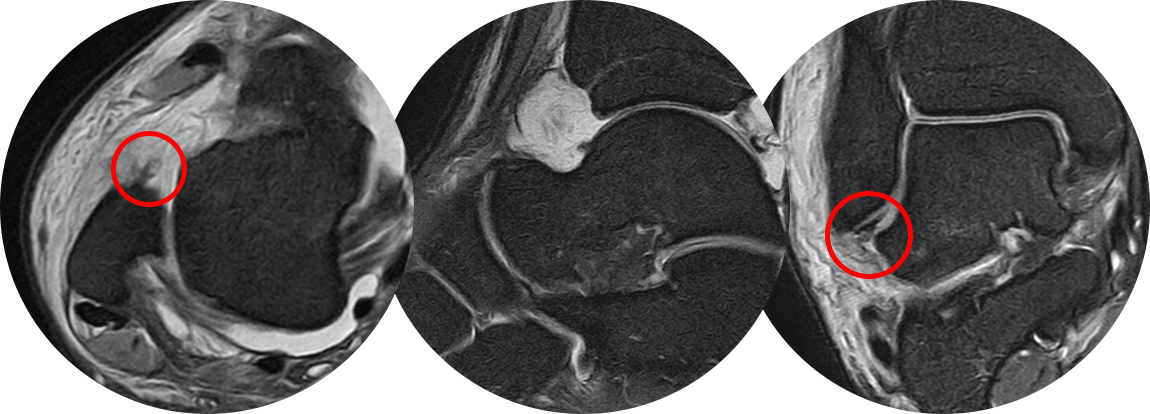

3도 손상의 경우 전거비인대 완전 파열 뿐만 아니라 종비인대의 손상도 흔히 같이 동반되어 있기 때문에

최소 절개를 통해 micro MBO 수술법을 이용하여 단단하게 인대를 봉합하여 재파열의 가능성을 최소로 낮춥니다.

수술 후 MRI 사진으로

좌측 사진에서 외측 복사뼈 부착 부위에서 완전 떨어졌던 전거비인대가 잘 봉합되어 있는 것을 볼 수 있고,

우측 사진을 통해 최소 절개를 통한 2개의 앵커 삽입을 통해 뼈에 인대를 넓게 부착을 시켜준 것이 확인됩니다.